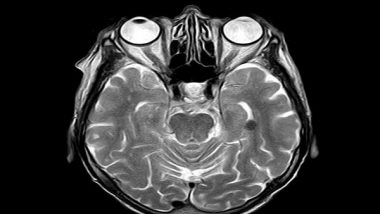

The new study, led by UCL Queen Square Institute of Neurology and National Hospital for Neurology and Neurosurgery at UCLH researchers and published in Brain, investigated 227 patients who had suffered either a brain tumour or stroke to specific parts of the brain, using the Raven Advanced Progressive Matrices (APM): the best-established test of fluid intelligence. The test contains multiple choice visual pattern problems of increasing difficulty. Each problem presents an incomplete pattern of geometric figures and requires selection of the missing piece from a set of multiple possible choices.

The researchers found that fluid intelligence impaired performance was largely confined to patients with right frontal lesions - rather than a wide set of regions distributed across the brain. Alongside brain tumours and stroke, such damage is often found in patients with a range of other neurological conditions, including traumatic brain injury and dementia.

Lead author, Professor Lisa Cipolotti (UCL Queen Square Institute of Neurology), said: "Our findings indicate for the first time that the right frontal regions of the brain are critical to the high-level functions involved in fluid intelligence, such as problem solving and reasoning.